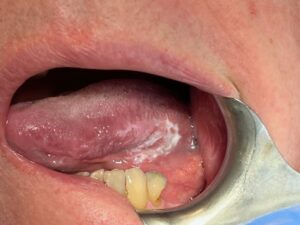

White patches – fear is often associated with any white patch, but there are many causes

Any white patch must be inspected, photographed, followed up and biopsied if needed

Leukoplakia: A condition marked by thickened, white patches on the gums, tongue, or inside the cheeks. It can be caused by chronic irritation, tobacco use, or other factors such as Frictionie biting, a rough tooth, or trauma. All leukoplakias should be reviewed, and a diagnosis made

Oral Lichen Planus: An autoimmune condition that affects the mouth, resulting in white, lacy patches and sores. This is common in women and can be associated with amalgam restorations